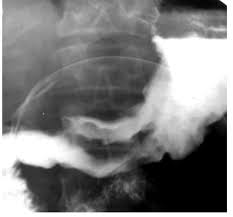

Методи вивчення травлення

Встанови

назву методу вивчення травлення, преставленого на зображенні:

рентгенівський метод

пальпація

гастроскопія

ультразвуковий метод